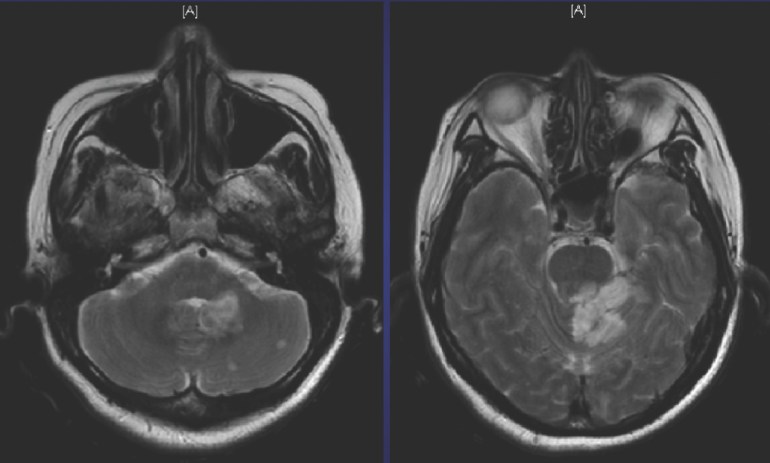

A middle-aged housewife with a history of chronic eczema and penicillin allergy (“rash and eye swelling”) presented with 2 days of fever, chills and lethargy. The initial clinical examination was unremarkable except for ongoing eczema and fever. The initial laboratory tests were remarkable only for mild thrombocytopaenia (114) and neutrophilia. However, she had chest pain 3 hours into hospitalisation, with mildly elevated cardiac enzymes (Troponin T = 0.55 ng/ml; normal CKMB), followed the next day by increased drowsiness with right gaze preference and mild neck stiffness. Repeat clinical examination in the intensive care unit (ICU) revealed a systolic cardiac murmur at the left sternal edge and a septic spot in her conjunctiva. An urgent MRI brain was arranged, showing multiple acute brainstem and cerebellar infarcts.

Given the blood culture of MSSA, cardiac murmur and the multiple embolic phenomena (conjunctival septic spot, brainstem and cerebellar infarcts), the diagnosis of MSSA infective endocarditis is highly likely. An echocardiogram (trans-oesophageal echocardiograms or TEEs have greater sensitivity and are generally recommended for MSSA bacteraemia) should be performed urgently, and surgical management (i.e. valve replacement) entertained if a large vegetation or valvular abscesses are found.